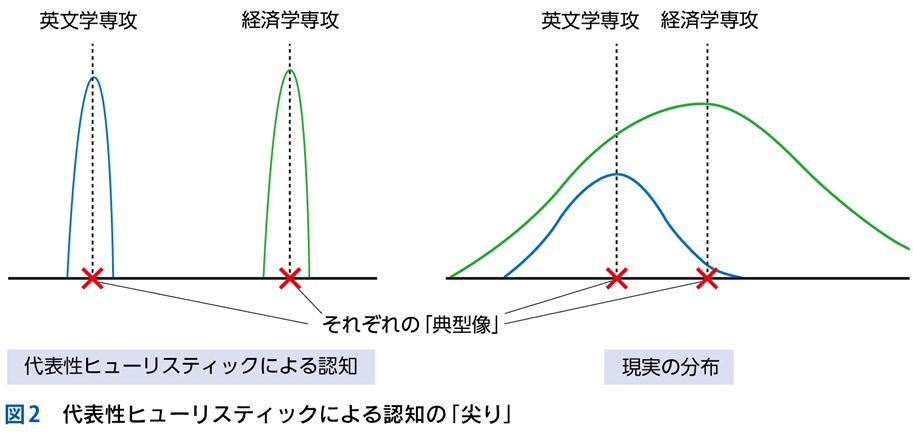

▶ システム1は確率計算をせず,「1か0か」の判断を瞬時に下す。印象的な患者背景があると,それを足掛かりにして「物語」の作成が始まり,その患者背景に疫学的に関連する疾患が決定的であるかのように直観してしまう(代表性バイアス+基準率無視)ので,診断の早期閉鎖につながる。

▶ システム2による分析的診断では,背景情報はあくまで基準率を規定するもの(可能な診断をすべて含むフレームの中で,各疾患の背景確率を提供するもの)であることを忘れず,患者背景に基づいてフレームを狭くしすぎることは避けなくてはならない。

▶ むしろ,特別な患者背景(疫学的リスク)の存在はフレームを拡大するものとしてとらえるとよい。

▶ たとえば,発熱患者に最近の渡航歴があれば,一般的な(渡航と関係しない)発熱の原因疾患に加えて渡航関連感染症を考える。免疫抑制状態にあれば,日和見感染というフレームを追加する。特殊な背景がある場合,その背景に紐づくフレーム内に鑑別を限定するのではなく,一般的な患者で設定するフレームは保持したまま,そこに患者背景によるフレームを付け加えるようにすべきである(図6)。